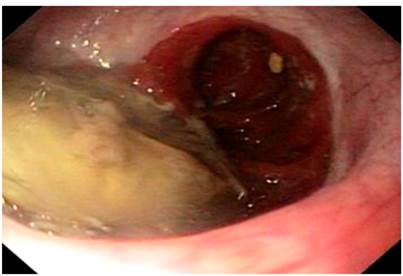

On physical examination, signs of dehydration were observed, with no other positive findings. In view of the history and symptoms described, an endoscopy of the upper digestive tract was performed. Food impaction was observed at the level of esophagojejunal anastomosis (Figure 1). A foreign body was removed, and an anastomosis was found, with no signs of tumor relapse. However, 10 cm from the anastomosis, a stenosis zone of 40% of the lumen was found, with a concentric decrease of the lumen due to a circumferential edema of the mucosa (Figure 2), which allowed the equipment to get in with a slight resistance, and biopsy samples were taken from the area.